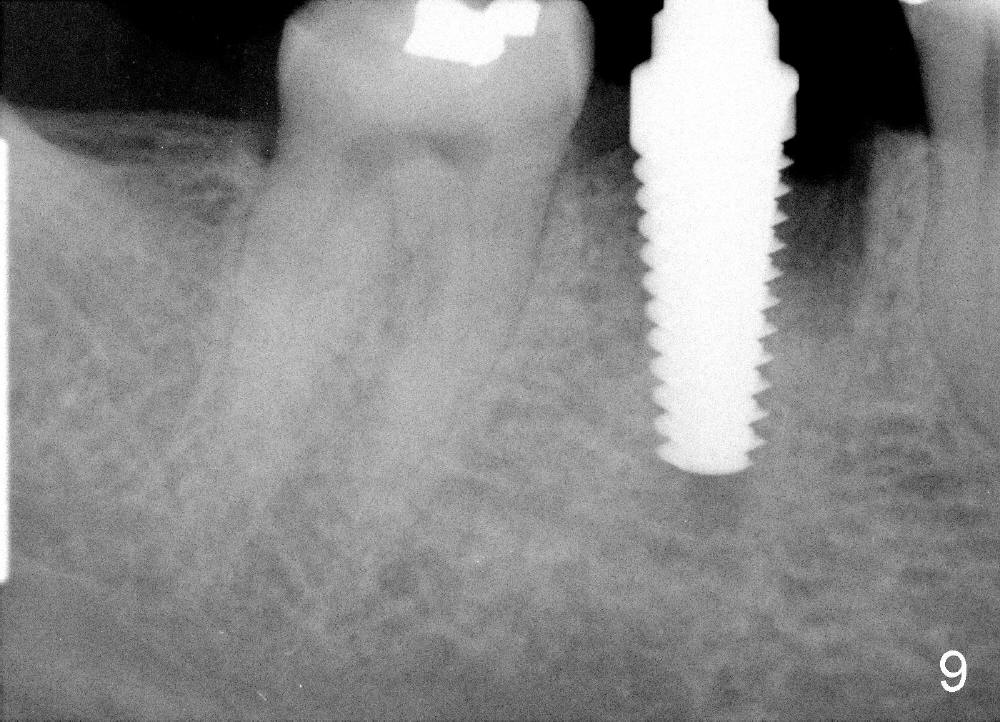

A 38-year-old lady agrees to have implant placement 7 years after loss of the crown of the lower right first molar (Fig.1,2). When the tooth is extracted, the septum is found to be low (Fig.3,4). To confirm it, a PA is taken (Fig.5). To initiate an osteotomy in the septum, it is trans-sectioned with thin osteotomes as shown in Fig.4 insert (black line). A 2 mm pilot drill is placed in the septum (Fig.6: P). The osteotomy is enlarged by 2.5-4.0 mm reamers (Fig.7,8), followed by insertion of 6x17 mm tapered tap at the depth 14 mm (Fig.9). The osteotomy is further enlarged by 4.5 and 5.0 mm reamers. A 6.0x14 mm one piece implant is placed initially. The trajectory is not ideal. A 6.0x14 mm one piece implant is placed initially. The trajectory is not ideal. The implant is removed from the osteotomy partially and reinserted with improved trajectory (Fig.11, compare to Fig.10 (red line)). Primary stability is high. There is not much bone mesiodistally so that the trajectory is easily changed in that direction. After abutment preparation, mixture of autogenous bone (harvested from reamers) and allograft is placed in the residual mesial and distal sockets (Fig.12). To contain the bone graft, an immediate provisional is placed (Fig.13 P). The occlusal plane of the provisional is significantly lower than that of the adjacent teeth to avoid micromovement of the implant. The patient is advised to eat soft food on the left side. Six days postop, the patient returns for prophy. The provisional is removed; the bone graft appears to be incorporating into the socket (Fig.14). After recementation, the provisional remains in place for 3.5 months; PA shows increased bone density in the mesial and distal sockets (Fig.15, compare to Fig.5,11). Due to insurance coverage, the patient defers fabrication of definitive restoration for at least 7 months. The immediate provisional is finally lost 8.5 months postop: the gingiva attaches to the 1-piece implant (Fig.16), while the density of the mesial socket increases (Fig.17 *) with formation of the cortex (lamina dura) coronally (v). Before the provisional (Fig.18 P) is removed for cementation of the definitive restoration, black shadow (*) is noted over the buccal gingiva. It is partially due to buccal placement (Fig.19) and partially due to buccal atrophy over a period of 10.5 months postop. How to prevent buccal placement? Positioning the first pilot drill in the septum buccolingually is a key. Eleven months post crown (Fig.20 C) cementation, the black shadow remains, but there is no tenderness. If the implant threads are immediately underneath the periosteum, there is tenderness.